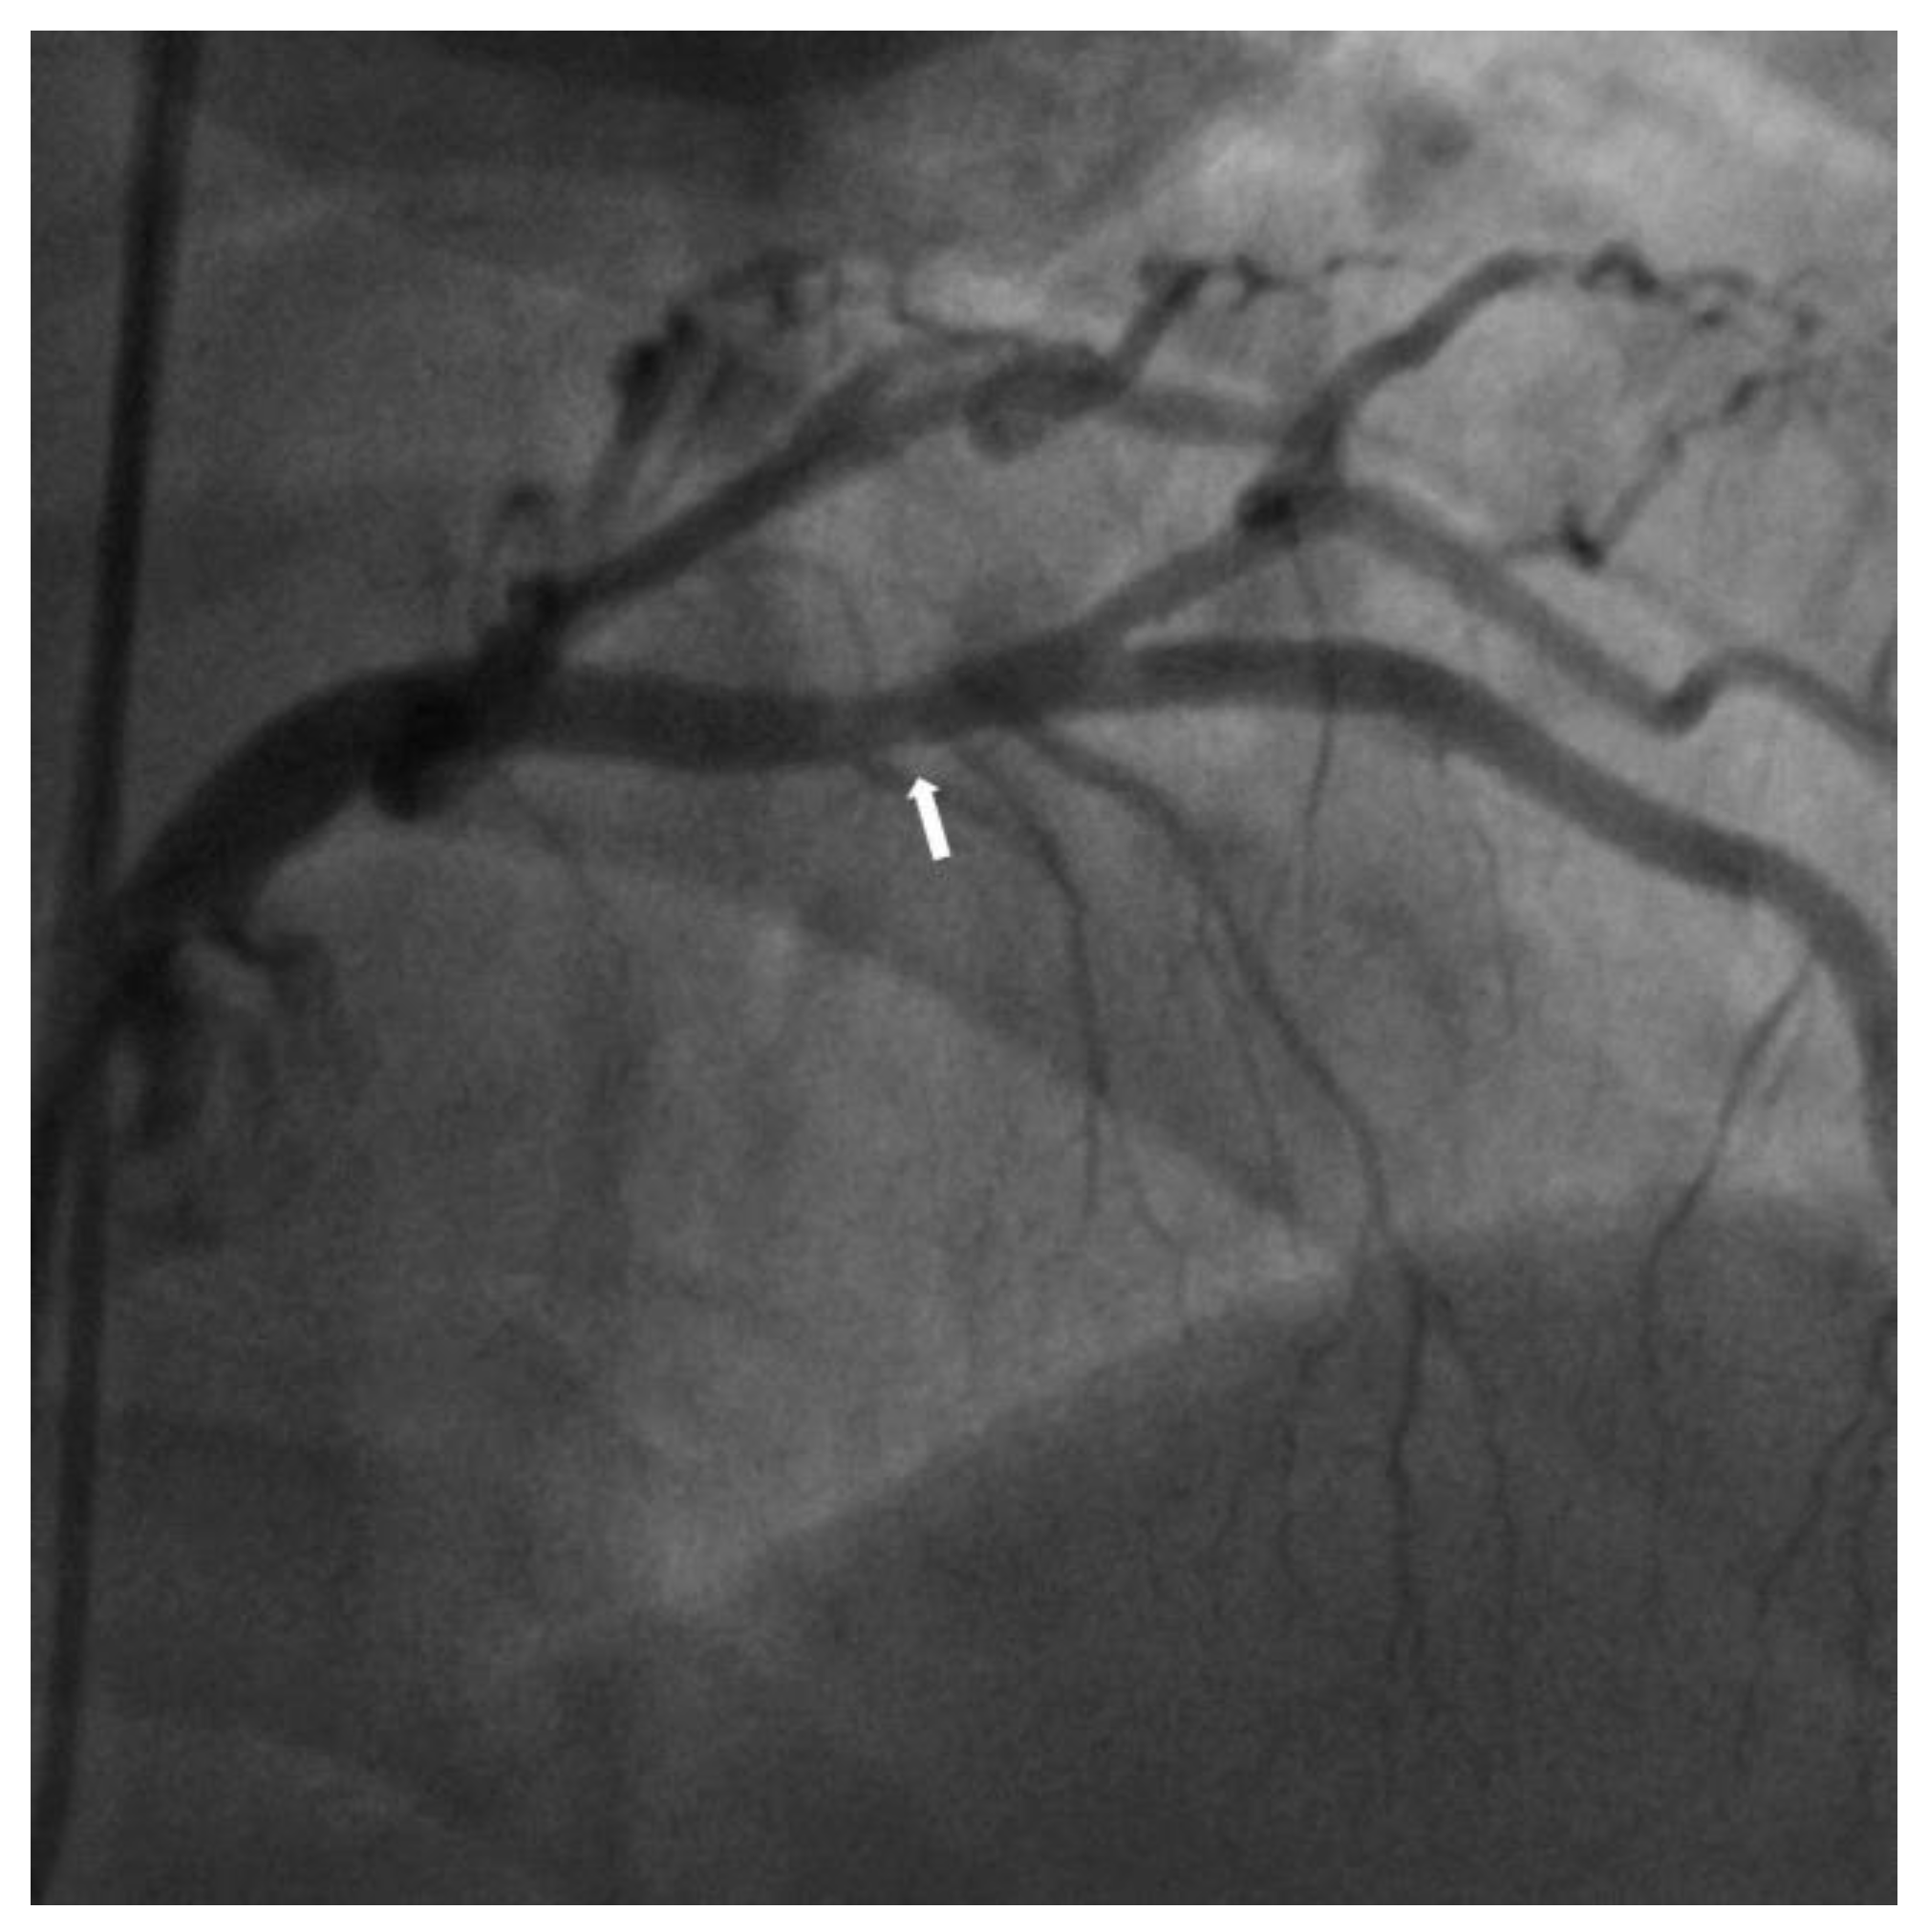

Near-Infrared Spectroscopy Intravascular-Ultrasound-Guided Intervention in Minimal Coronary Artery Stenosis: A Case Report

2. Case Report